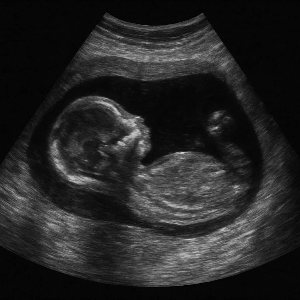

고위험 임산부이신가요?

임신 중 고위험 진단을 받아 입원치료를 받았거나 예정이시라면,

2025년부터는 소득에 관계없이 의료비의 90%까지 지원받을 수 있다는 사실, 알고 계셨나요?